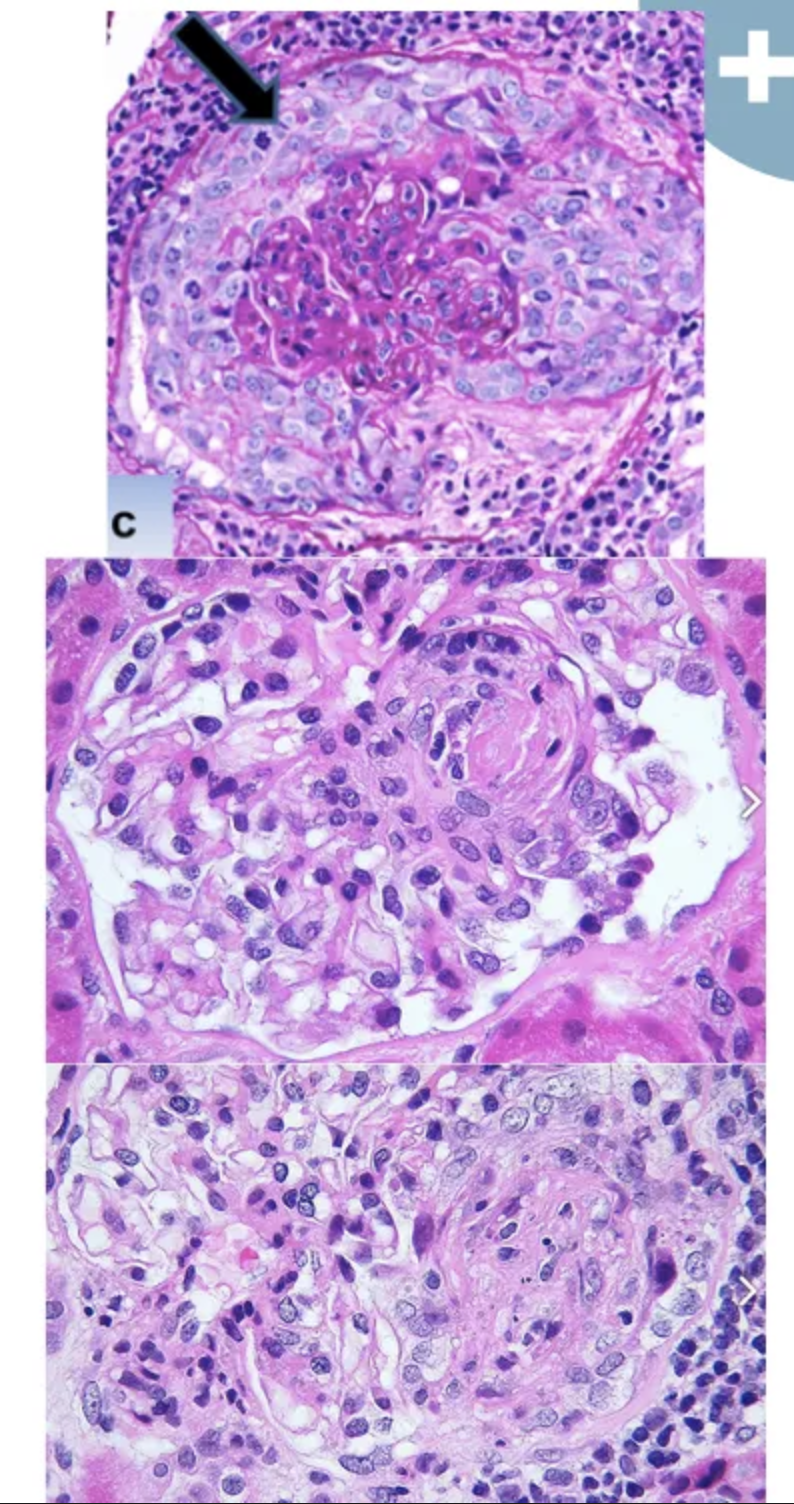

Cómo se ven los glomérulos en la glomerulonefritis infecciosa?

Glomérulos hipercelulares de gran tamaño

Infiltración de leucocitos (es global y difuso osea en tdoso los lóbulos de todos los glomérulos)

Proliferación de células endoteliales y mesangiales

Formación de semilunas

En la inmunofluorescencia de la glomerulopatia infecciosa, que depósitos célulares se pueden ver?

IgG

C3

C4

C5 - C9

Si la glomerulonefritis rápidamente progresiva es la tipo 2, cómo se verá en inmunofluorescencia?

Granular

En la microscopía electrónica que es lo que más hace que se distinga de la glomerulopatia infecciosa?

Depósitos definidos, amorfos y electrodensos en la vertiente epitelial de la membrana a modo de JOROBAS